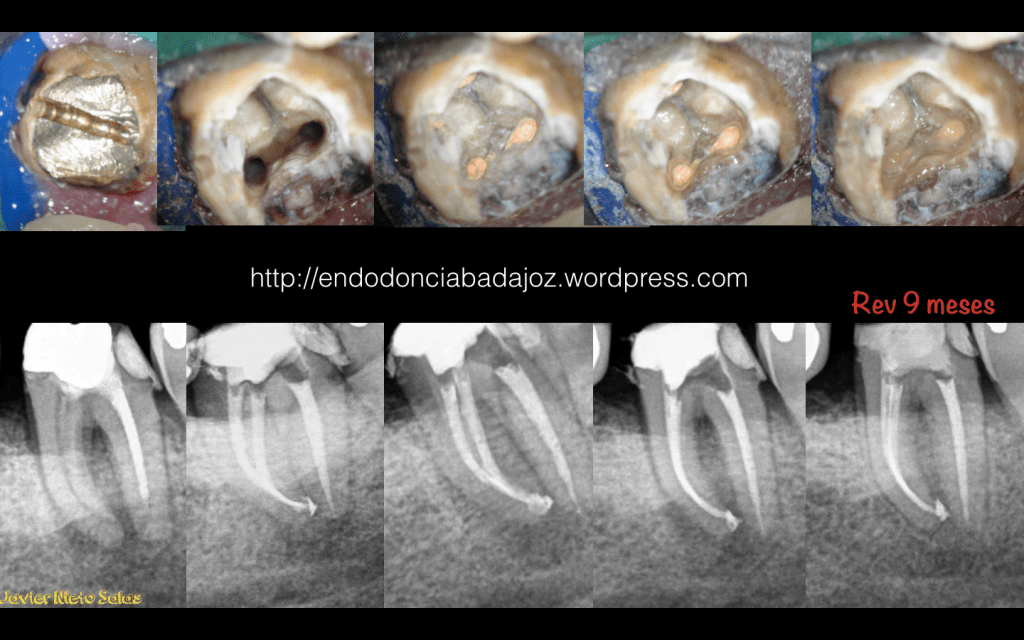

Como veremos en estos dos casos que subimos hoy, si realizamos un tratamiento correcto, que nadie dice que sea sencillo, obtendremos , en la generalidad de los casos, un MUY BUEN PRONÓSTICO.

1) Caso A: Motivo de fracaso, subobturación de los conductos mesiales. Vemos como corrigiendo el problema, es un tratamiento predecible